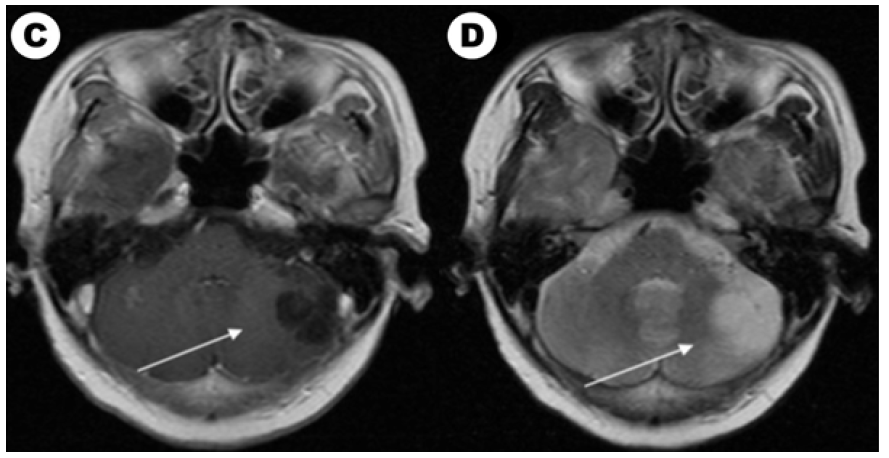

Figure 1A: The brain enhanced MRI of a 61-year-old woman with non-small lung cancer and EGFR 21L858R mutation before and after EGFRTKI treatment. Contrast-enhanced T1-weighted MR image in baseline. Figure 1B: Contrast-enhanced T2-weighted MR image in baseline.

Figure 1C: Contrast-enhanced T1-weighted MR image after EGFR-TKI target therapy and whole brain radiotherapy (the prescription dose and fraction schedule were 30Gy/10F) treatment one month. Figure 1c: Contrast-enhanced T2-weighted MR image after EGFR-TKI target therapy and whole brain radiotherapy treatment one month.

According to our follow-up, 4 patients abandoning therapy and 33 patients which received treatment had evaluable efficacy. Until the last follow-up time, 40 patients had evaluated overall survival and 8 (8/40, 20.0%) patients were still alive. Among them, 14 patients with EGFR/ALK gene mutated had TKI targeted treatment and 19 patients received chemotherapy. For brain radiotherapy, 4 of 14 EGFR/ALK mutated patients received radiotherapy and 12 of 19 patients received chemotherapy had brain radiotherapy. We also compared characteristics between patients received targeted drugs and chemotherapy in (Table 2). We showed a typical case of cystic BM which was EGFR mutated NSCLC patient in (Figure 1A). We showed the baseline brain MRI images in(Figure 1A) (T1-weighted MR image) and(Figure 1C) (T2-weighted MR image). After one month of icotinib-targeted therapy and whole brain radiotherapy, the brain MRI images of the patient presented in (Figure 1C) (T1-weighted MR image) and (Figure 1C) (T2-weighted MR image). The effect+- -+-+-+++-` of this patient showed that the brain lesion had shrunk significantly.